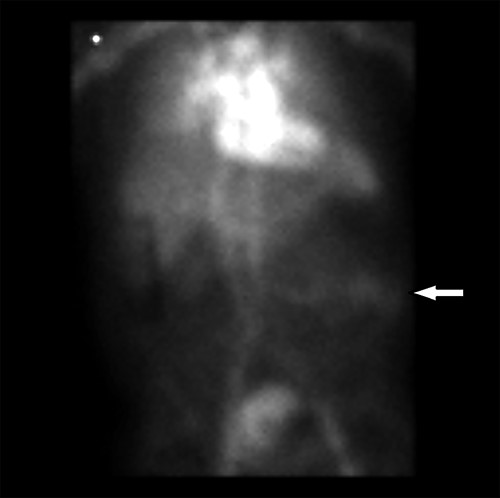

At the time of his PET scan, the patient acutely developed diffuse abdominal pain and vomiting. The scan was aborted and the patient was rushed to the emergency department. An abdominal X-ray and a CT scan of the abdomen and pelvis showed small bowel dilatation, but there was no intestinal mass lesion (Fig. 1). He was placed on nasogastric tube decompression. The patient reported having melena that morning. The hemoglobin was found to be 6.1 g/dl and a tagged RBC nuclear scan showed active gastrointestinal bleeding (Fig. 2) at the approximate location of the transition zone of the small bowel obstruction seen on CT.

CT of the abdomen and pelvis showing evidence of small bowel obstruction with dilated stomach and loops of the small intestine.